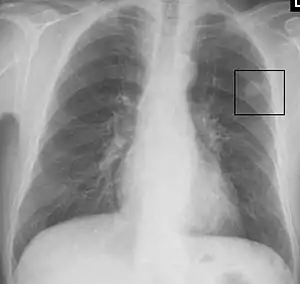

In LEMS associated with lung cancer, most have no suggestive symptoms of cancer at the time, such as cough, coughing blood, and unintentional weight loss.[2] LEMS associated with lung cancer may be more severe.[4]

LEMS is often associated with lung cancer (50–70%), specifically small-cell carcinoma,[3] making LEMS a paraneoplastic syndrome.[4] Of the people with small-cell lung cancer, 1–3% have LEMS.[2] In most of these cases, LEMS is the first symptom of the lung cancer, and it is otherwise asymptomatic.[2]

Blood tests may be performed to exclude other causes of muscle disease (elevated creatine kinase may indicate a myositis, and abnormal thyroid function tests may indicate thyrotoxic myopathy). Antibodies against voltage-gated calcium channels can be identified in 85% of people with EMG-confirmed LEMS.[3] Once LEMS is diagnosed, investigations such as a CT scan of the chest are usually performed to identify any possible underlying lung tumors. Around 50–60% of these are discovered immediately after the diagnosis of LEMS. The remainder is diagnosed later, but usually within two years and typically within four years.[2] As a result, scans are typically repeated every six months for the first two years after diagnosis.[3] While CT of the lungs is usually adequate, a positron emission tomography scan of the body may also be performed to search for an occult tumour, particularly of the lung.[6]